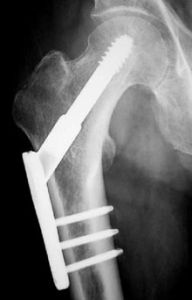

骨接合術骨接合術起初基本用於骨折,但是隨著科技的發展以及新的技術的發明,骨接合術的用還會用於整形手術。

本發明涉及一種用於骨接合術的,特別是用於採用一塊支撐板來固定骨的碎片的緊固元件。為了實現一種經得住劇烈的應力和容易拆除的緊固,這種緊固元件包括一個設有一個凸緣的塞套和一個與塞套嚙合的螺釘。塞套內孔後部直徑比螺釘的螺紋外徑稍小一點,而內孔前部的直徑則小於螺釘的螺紋底徑。